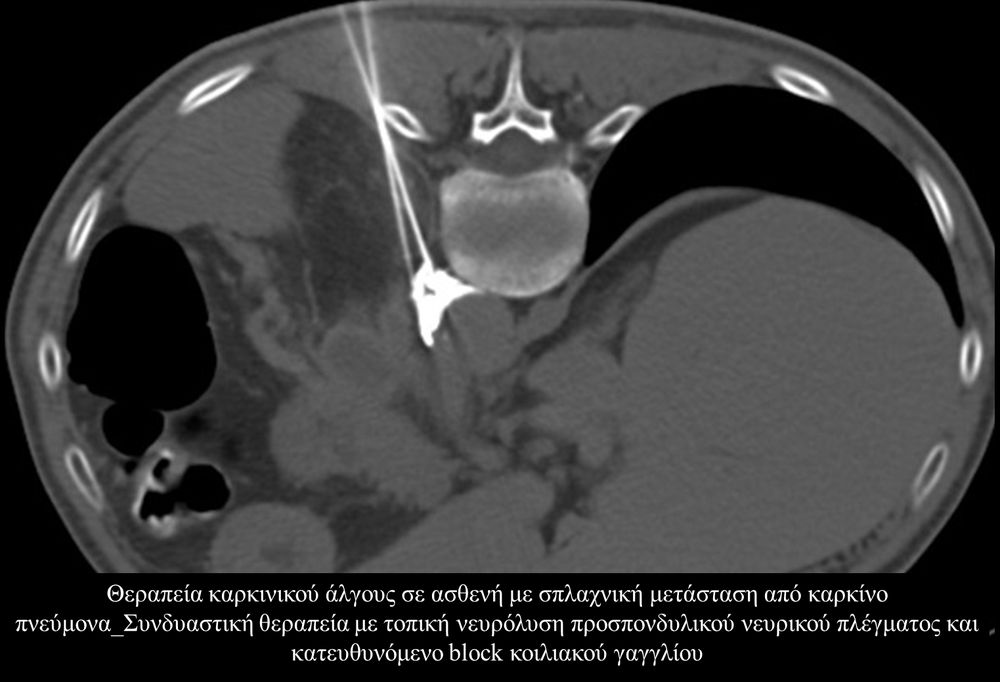

Η αντιμετώπιση του καρκινικού πόνου, εκτός από την κλασική συντηρητική φαρμακευτική θεραπεία, όταν ο πόνος επιμένει ή όταν οι παρενέργειες των φαρμακευτικών μεθόδων εξαντλούν τον ασθενή, περιλαμβάνει ελάχιστα παρεμβατικές τεχνικές με τις οποίες επιτυγχάνεται διακοπή ή καταστροφή της νευρικής οδού μεταβίβασης του πόνου. Η επεμβατική ακτινολογία διαθέτει μια πληθώρα θεραπευτικών τεχνικών που σκοπό έχουν να προσφέρουν ποιοτική βελτίωση της ζωής και των σχέσεων, τόσο των ογκολογικών ασθενών, όσο και των οικογενειών τους.